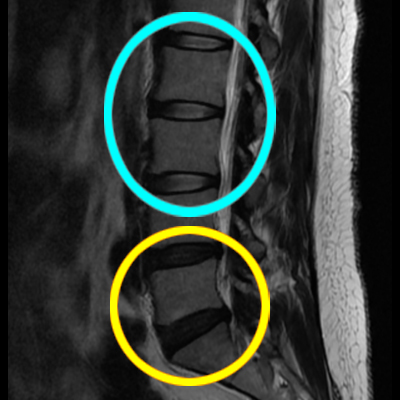

교통사고 후 mri 촬영내용에서

요추5번 및 천추 사이 디스크가

심각하게 돌출된 것이 보여집니다.